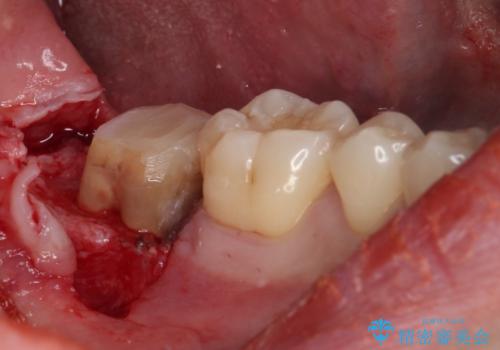

レントゲン撮影より、根尖部に病変が認められたため、根管治療を行った後に、歯冠長延長術を行うこととしました。

銀歯の頃は頻繁に外れていたため、不快感が強かったようですが、歯冠長を延長したことで外れにくいクラウンを装着することができ、不快感が改善されました。